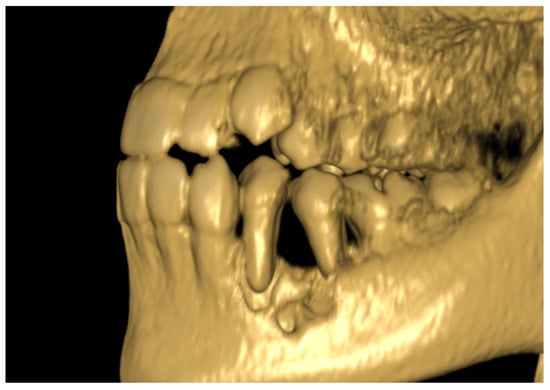

The 11-year-old patient was referred to the Children’s Dental Clinic with suspected inflammation of the periapical tissues of the region of the left premolar of the mandible. Clinical evaluation revealed hypermobility of teeth 34 and 35 (FDI) with enlargement and redness of gingival tissue of both the vestibular and lingual side of the alveolus with pain symptoms. Teeth with no signs of caries lesions were not tender to percussion, the vitality tests were inconclusive, and no palpable lymphadenopathy was noticed. A cone beam computed tomography (CBCT) examination (NewTome 3G, QR Verona, Italy, 110 kV, 2 mA, 18 s) revealed root resorption of tooth 35 and an area of extensive demineralisation in the region of 33–36 with loss of trabecular bone pattern, destruction of buccal, and thinning of the lingual cortical plates (Figure 1, Figure 2 and Figure 3). On the basis of the clinical examination and the unusual features of the X-ray examination, the diagnosis was extended to include a biopsy of soft and hard tissue. A histological examination revealed Burkitt’s lymphoma. An extent examination using 2-deoxy-2-[fluorine-18] fluoro- D-glucose integrated with computed tomography (18F-FDG PET CT), magnetic resonance imaging (MRI), and ultrasonography (USG) revealed a disseminated tumour process with infiltrates in the left palatine tonsil, head of the pancreas, stomach wall, and right pleura. On the basis of the results of the extended examination and according to the European Intergroup for Childhood Non-Hodgkin Lymphoma (EICNHL-COG Inter-B-NHL-2010) therapeutic protocol, the patient was classified into the B-High therapeutic group, and a 7-day cytoreductive prephase COP (Encorton, Cyclophosphamide, and Vincristine) was initiated. After completing the prephase, significant regression of the primary lesion was observed. Subsequently, the patient completed two cycles of R-COPADM (Rituximab, Vincristine, Methotrexate 3 g/m2, Cyclophosamide, Doxorubicin, and Encorton) and two cycles of R-CYM (Rituximab, Encorton, Methotrexate, and Cytarabine) treatments. The patient responded well to treatment, and remission was achieved. Now, five years after initial diagnosis, he is undergoing regular check-ups, including dental examinations. The intraoral lesion resolved completely because of chemotherapy, and no surgical treatment was performed (except for initial biopsy taking).

Figure 3. Patient, 11 y.o.: Panoramic reconstruction from CBCT examination. Rarefication of cancellous bone in the apical region of tooth 35 with apical resorption and the appearance of “floating in the air”.